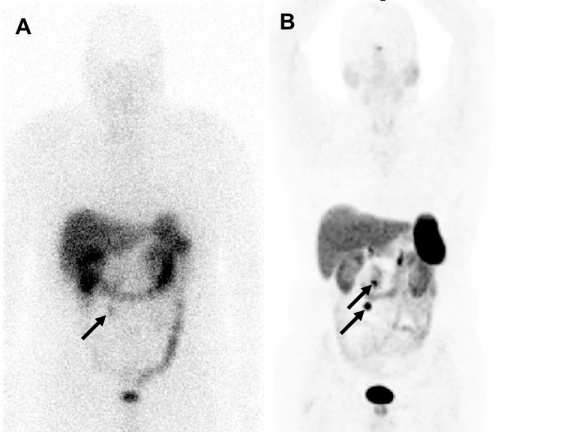

68Ga-DOTATATE, a synthetic somatostatin analog, binds eight times more strongly than the existing imaging agent, 111In-pentetreotide, to somatostatin receptors found in neuroendocrine tumors (NETs) in adult and pediatric patients.

Seventy-eight patients participated in the clinical trial, which found that 68Ga-DOTATATE, when compared with 111In-pentetreotide, produced higher quality images in a significantly shorter period of time and also reduced the patient’s overall radiation exposure. The use of 68Ga-DOTATATE improved treatment for 36 of the 78 (46 percent) patients, with no adverse side effects of the imaging agent requiring treatment.

“Given the lack of significant toxicity, lower radiation exposure and improved accuracy, the investigation concluded that 68Ga-DOTATATE imaging should be used instead of 111In-pentetreotide imaging where available,” said Ronald Walker, M.D., Professor of Clinical Radiology and Radiological Sciences.

In its announcement, the FDA stated that early detection of NETs in adults and children is critical, and that the data presented in the study confirmed the success of 68Ga-DOTATATE imaging in locating NETs in adults and children.